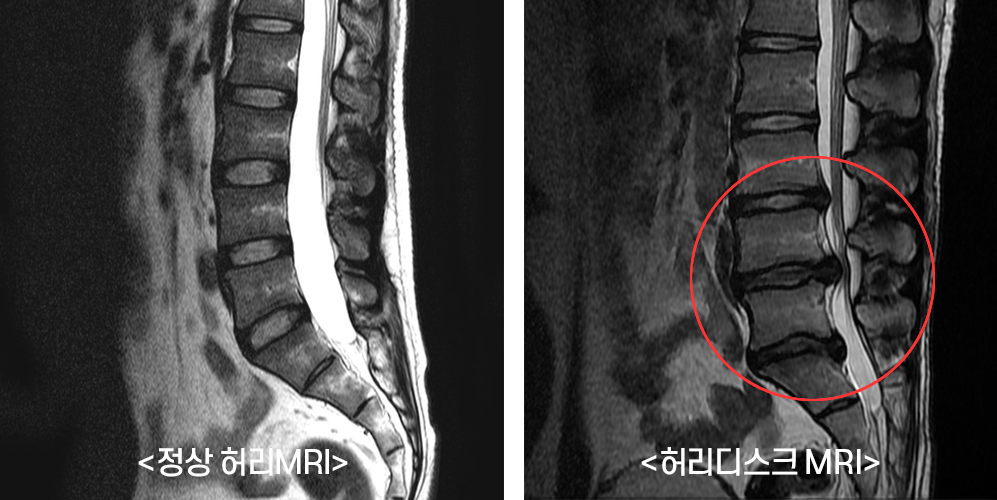

허리 협착증은 주로 노화에 따른 퇴행성 변화, 유전적 요인, 그리고 과도한 운동 등 다양한 원인으로 발생합니다. 허리의 디스크가 변형되거나 척추관이 좁아짐으로써 신경이 압박받고, 이는 심한 통증으로 이어질 수 있습니다.